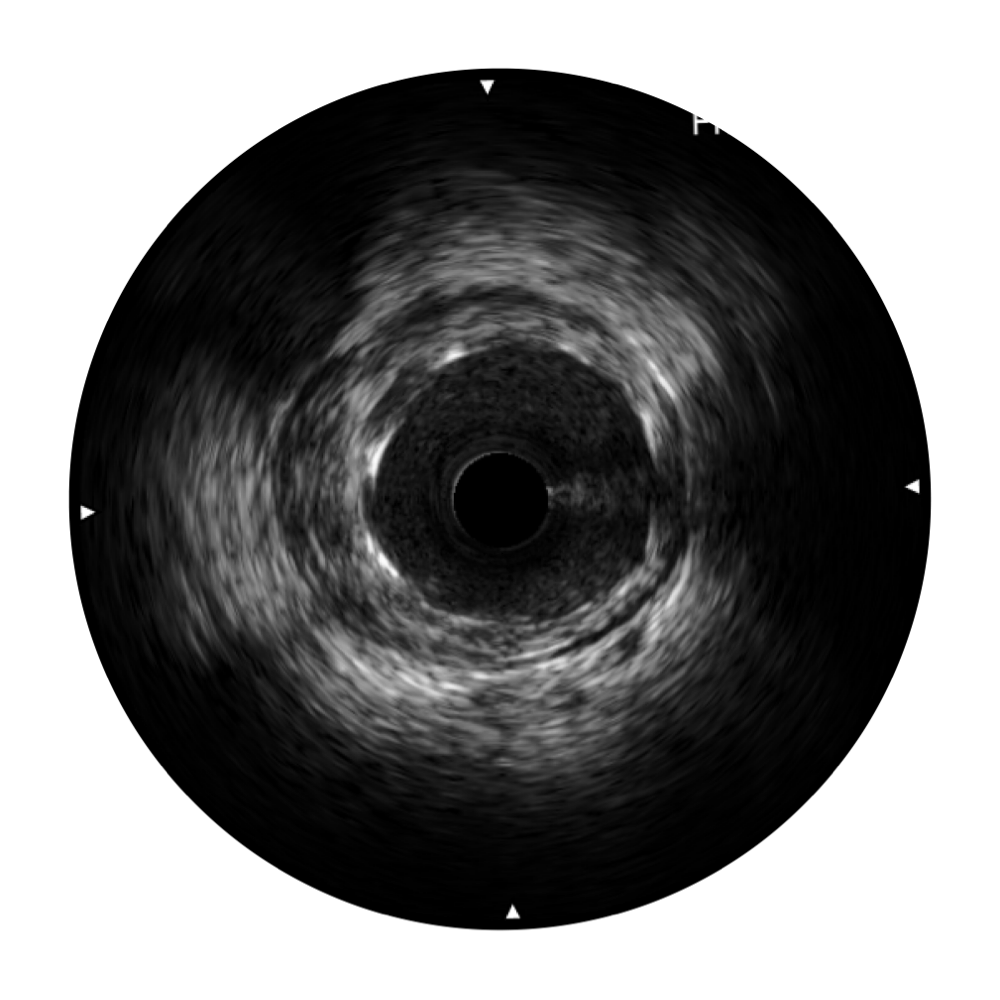

传统IVUS图像

对比传统IVUS导管成像,银河集团官网宽频IVUS图像的近场支架梁显影更细腻,远场中膜外血管仍清晰可辨,兼顾远中近,兼顾分辨力与穿透深度